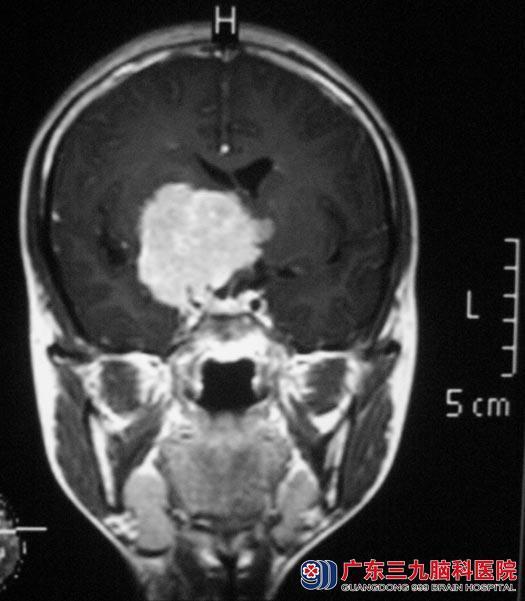

同学们开始帮着小惠找医院,经过不断的咨询,她们选择了广东三九脑科医院。头颅MR检查提示肿瘤大小约42.0mm×47.5mm×45.8mm,邻近脑室受压,三脑室明显受压变窄,右侧侧脑室受压,中线结构左偏。邻近视交叉右侧显示不清,右侧海绵窦部分边缘与病史分界不清。